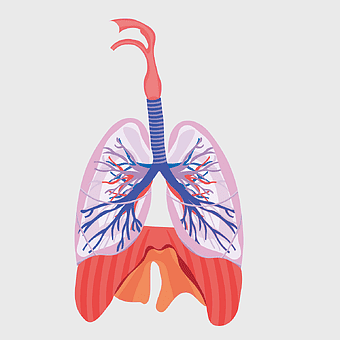

Pulmonary edema symptoms, chronic obstructive pulmonary disease diagram, kidney failure effects on lungs, pulmonary circulation illustration, lung disease diagnostic, respiratory health visuals, human anatomy respiratory system, PNG

- pulmonary edema symptoms

- chronic obstructive pulmonary disease diagram

- kidney failure effects on lungs

- pulmonary circulation illustration

- lung disease diagnostic

- respiratory health visuals

- human anatomy respiratory system

lungs illustration, respiratory system diagram, idiopathic pulmonary fibrosis, breathing anatomy, pulmonary health, respiratory tract function, lung disease awareness -

lungs illustration, respiratory system diagram, human lungs anatomy, pulmonary alveolus structure, bronchial tree visualization, trachea and bronchi, lung lobes detail -

Respiratory system anatomy, human breathing process, pulmonary alveoli structure, respiratory therapist training, respiratory health education, lung function diagram, respiratory disease prevention -

human lung anatomy, respiratory system illustration, heart and lungs diagram, bronchus structure, pulmonary function, thoracic cavity, medical imaging analysis -

lung organ, small lungs, respiratory system, pink trachea, human anatomy, medical illustration, pulmonary health -